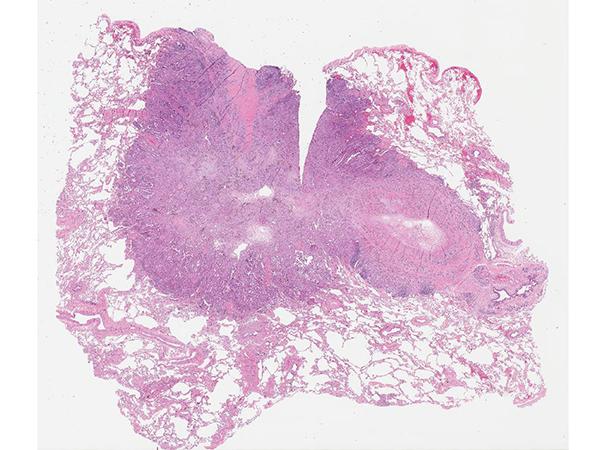

Clinical History: A 68-year-old man with 2 lung nodules underwent right middle lobectomy for a 2 cm nodule and a wedge resection of a 1 cm nodule in the right upper lobe. All hilar and mediastinal lymph nodes were negative. Photomicrographs from the right middle lobe nodule are shown in Figures 1 and 2. The right upper lobe nodule is shown in Figures 3 and 4.

In this case, both lung adenocarcinomas were submitted for next-generation sequencing (NGS) for EGFR, KRAS, MET, BRAF, HER2, as well as testing for ALK (D5F3 immunohistochemistry), ROS1 (FISH) and RET (FISH). The adenocarcinoma in the right middle lobe was found to be wild-type (no driver mutation), while the adenocarcinoma in the right upper lobe had a KRAS driver mutation (KRAS c. 34G>T, p. Gly12Cys in exon 2). Based on this result, the 2 adenocarcinomas were diagnosed as separate synchronous primaries, and each was staged separately with its own synoptic template (pT1bN0 and pT1aN0).